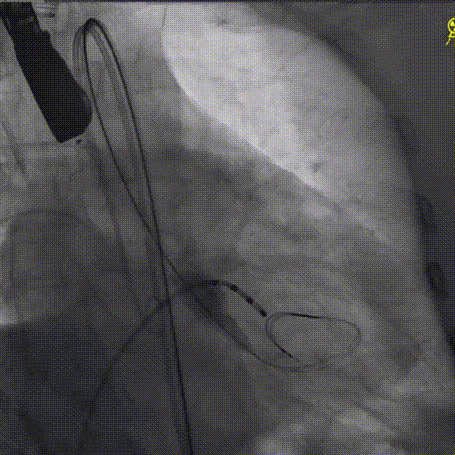

经左股动脉穿刺,置入6F股动脉穿刺鞘,将猪尾导管引导至主动脉根部,行主动脉造影。

术前主动脉造影